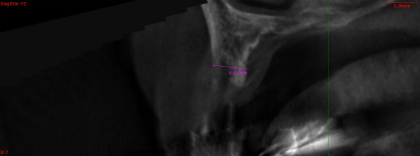

• インプラント